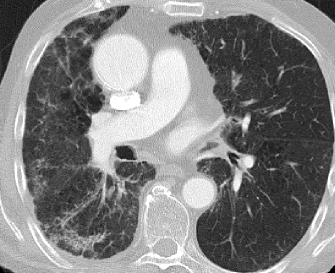

![]() |

The used data set consists of chest scans of 14 patients with known occurrence of honeycombing patterns. For each patient, a stack of 70 axial images reconstructed with a lung kernel from high-resolution computed tomography (HRCT) of the chest was assessed by an experienced radiologist (Fig. 1). The resulting images are comparable to classical HRCT with the exception that reconstructions of a small number of slice positions are also available. All images have a slice thickness of 1mm, an in-plane pixel size of 0.69x0.69 mm, and a slice distance of 5 mm. In this data set, 241 square, 2-dimensional ROIs with an edge length of 21 pixels were defined in 152 healthy and 89 pathological pattern occurrences in lung tissue (Fig. 2). In each of these ROIs, the set of the following feature vectors of texture descriptors were calculated.